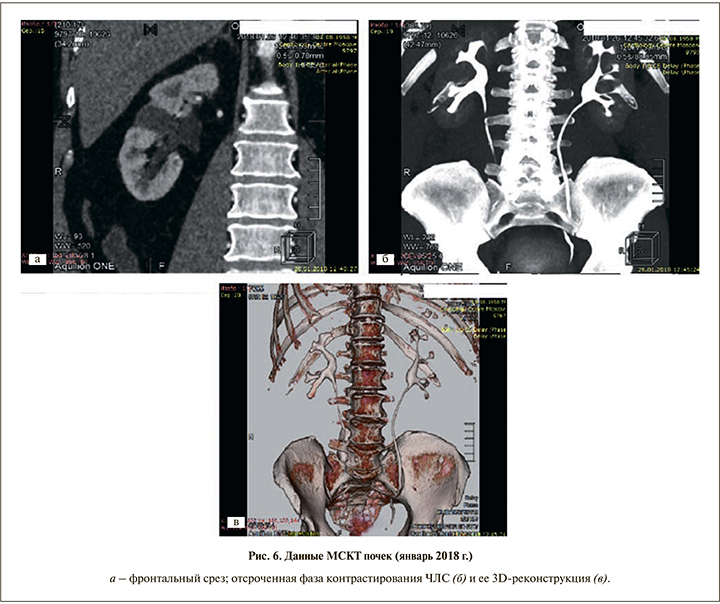

Последнее обследование, которое пациент прошел в январе 2018 г., включило общеклинические анализы крови и мочи; определение уровня простатспецифического антигена (ПСА); МСКТ органов брюшной полости и мочевыделительной системы. В общем анализе крови: Hb – 172 г/л, гематокрит – 53,3, эр. – 5,96 1012/л, ЦП – 0,89, тр. – 249 109/л, л. – 8,45 109/л, н. – 36,8%, э. – 1,9%, лимф. – 53,6%, м. – 6,9%, СОЭ – 7 мм/ч. В общем анализе мочи: белок отсутствует, эритроциты – 1, лейкоциты – 1, слизь, бактерии отсутствуют, ПСА общего 2,76 нг/мл. Данные МСКТ (26.01.2018): в среднем сегменте правой почки определяется кистозное образование 20х17 мм, которое полностью замещает паренхиму почки. После внутривенного контрастирования накопления контрастного препарата данной структуры не определяется, плотность во все фазы составляет 8–14 HU (рис. 6).